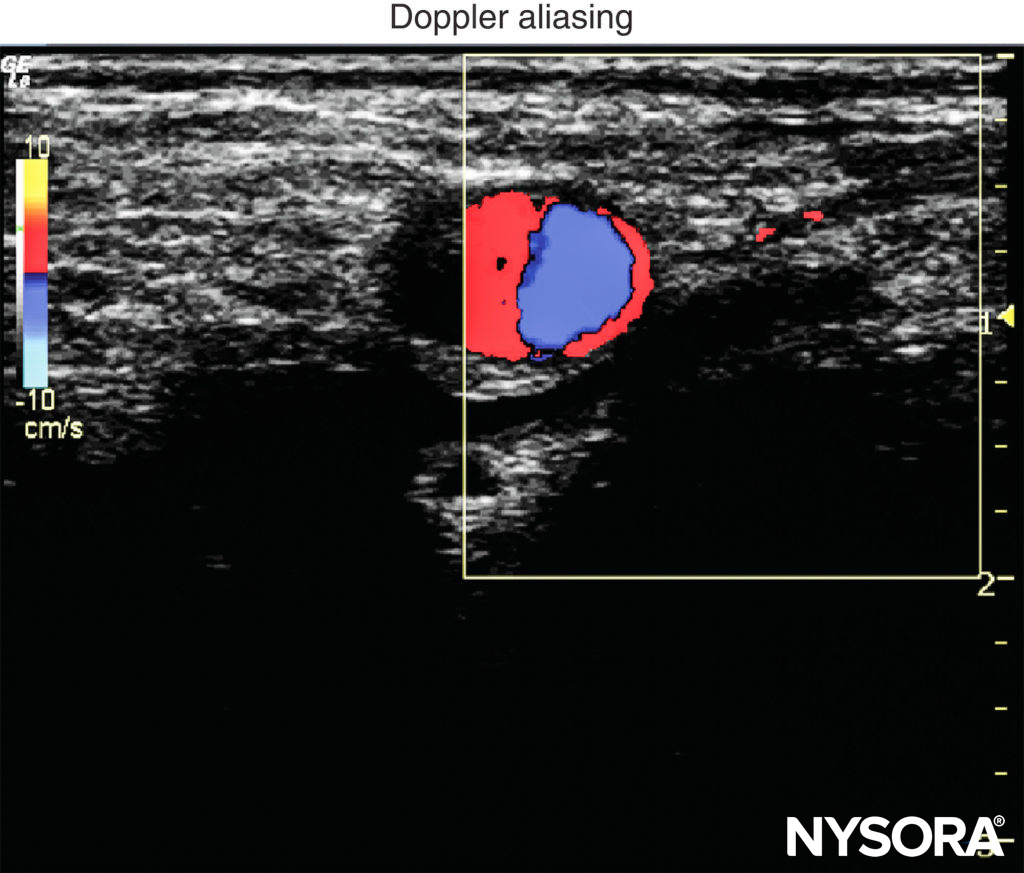

5. Doppler: In regional anesthesia, Doppler ultrasound is used to detect vascular structures or the location of the spread of the local anesthetic injection. Doppler velocity scale is best set between 15 and 35 cm/s to reduce aliasing of color Doppler imaging and artifacts of color (Figure 5). Of note, power Doppler is more sensitive for detecting blood flow than color Doppler. The gate size is another common setting when color Doppler is used. It should be as small as possible to overlay the area of interest. An appropriate small gate not only can exclude distractive signals from adjacent tissues but also can improve temporal resolution by increasing the frame rate.

FIGURE 5. Color Doppler aliasing occurs when the velocity scale for color Doppler is set too low.